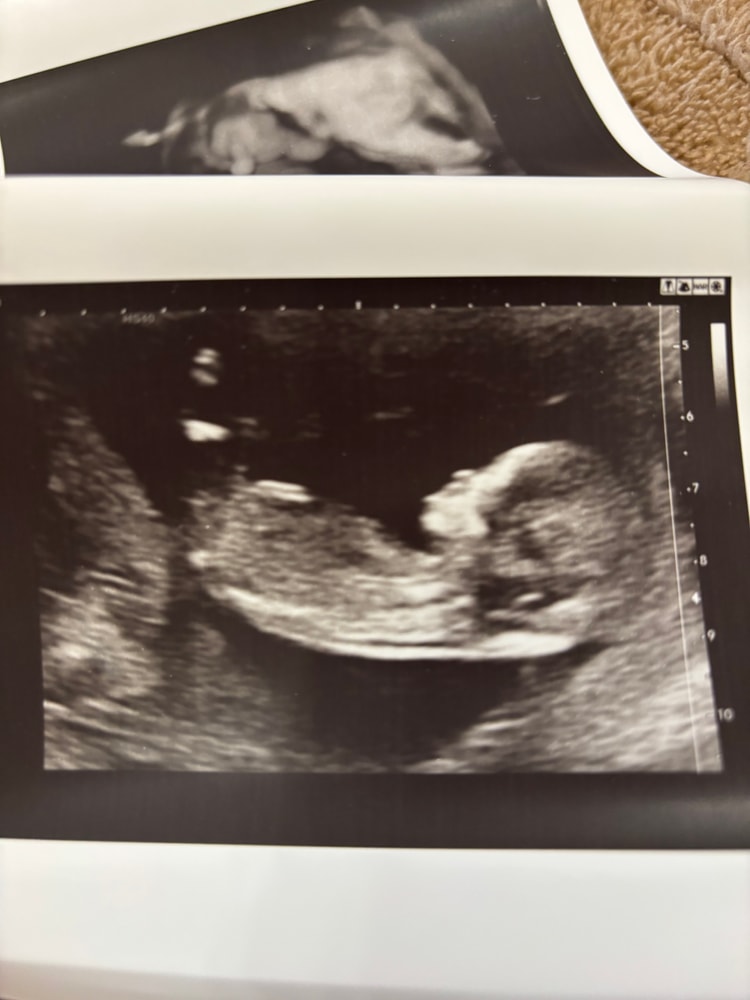

1 скрининг💙

Анализы, скринингиНа днях сходили платно на скрининг вместе с мужем, ибо в жк сказали сразу, что там на скрининг никого, кроме меня не пустят🙈 А мне очень уж хотелось сходить вместе.

По итогу все хорошо, посмотрели все супер внимательно, все рассказали и показали. Малыш сначала спал, лежал тихонько, а потом, видимо, мы его разбудили, начал отплясывать там и рукой махать😁 Пол, кстати, подтвердили сразу, ну, мы и сами все увидели, парень оказался не из скромных😂

Как обычно дали кучу фотографий, послушали сердечко, эмоции остались абсолютно положительные🙌🏻